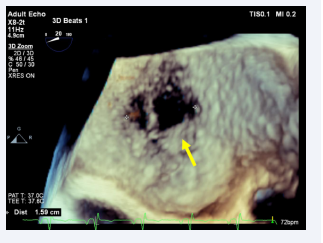

The anterior rim is 8 to 9 mm thick, the posterior rim is 18 mm thick, the distal rim is 17 mm thick, and the proximal rim is 17 mm thick. TEE, showed markedly dilated left atrium (LA). There is a fenestrated defect at the mid IAS with two left-to-right flow jets, the larger of which is 8 mm x 8 mm and the smaller of which is 5 mm x 8 mm, separated by a thin membrane (Figure 5).

Three-dimensional TEE, Mid-esophageal level, 4-chamber  view (20o), demonstrates the large fenestrated ASD Secundum type.

Figure 5: Three-dimensional TEE, Mid-esophageal level, 4-chamber view (20o), demonstrates the large fenestrated ASD Secundum type.

The total defect diameter was 15 mm x 8 mm, the rim thickness was 19 mm proximally and distally, the anterior rim was 8 mm thick, the posterior rim was 13 mm thick, and the superior and inferior rims were 12 mm and 14 mm thick, respectively. The ASD looks like Swiss cheese at 1 O’clock and a band in the middle, and it measures 8 x 8 mm and 8 x 5 mm, about 15 to 16 mm in diameter. She has significant RV dilatation and RA dilatation, with a Qp/Qs ratio of 3.0.